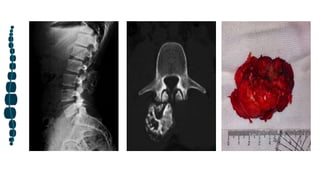

Quiste óseo aneurismático

El quiste óseo aneurismático (ABC) suele afectar a pacientes <20 años de edad, con leve

predilección femenina. En general, 12 a El 30% de los ABC se encuentran en la columna vertebral.

La columna torácica es la más segmento frecuentemente afectado; La afectación lumbar y cervical

es menos común. Aunque es muy raro, el ABC sacro es centrado en segmentos superiores, similar

al tumor de células gigantes (GCT).

Los ABC espinales suelen mostrar una marcada remodelación expansiva (►Fig. 5). Aunque

centrado en los elementos posteriores, 75 a 90% de los casos se extienden hacia el cuerpo

vertebral.

La tomografía computarizada y la resonancia magnética de un ABC primario muestran una o más

comúnmente, múltiples niveles de líquido que representan hemorragia con sedimentación.18 Durante

la obtención de imágenes de sección transversal, puede ser necesario colocar su pino durante 10

minutos para detectar niveles de líquidos.

La resonancia magnética también es indispensable para determinar la extensión de la lesión y la

relación con el canal central y raíces nerviosas, como en todos los tumores espinales.

Metahemoglobina dentro de los componentes del fluido muestran un aumento de señal en ambos

Imágenes de RM potenciadas en T1 y potenciadas en T2. Un bajo El borde de intensidad de la señal

en todas las secuencias de pulsos corresponde a un membrana perióstica intacta y a menudo

engrosada borde delgado